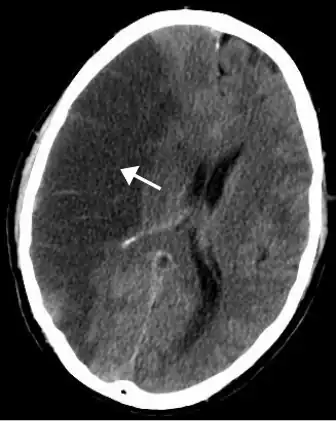

![]() | |

| CT scan of the brain showing a massive, prior right-sided ischemic stroke from blockage of an artery. Changes on a CT may not be visible early on.[1] | |

The most significant risk factor for stroke is high blood pressure.[7] Other risk factors include high blood cholesterol, tobacco smoking, obesity, diabetes mellitus, a previous TIA, end-stage kidney disease, and atrial fibrillation.[2][7][8] Ischemic stroke is typically caused by blockage of a blood vessel, though there are also less common causes.[13][14][15] Hemorrhagic stroke is caused by either bleeding directly into the brain or into the space between the brain's membranes.[13][16] Bleeding may occur due to a ruptured brain aneurysm.[13] Diagnosis is typically based on a physical exam and supported by medical imaging such as a CT scan or MRI scan.[9] A CT scan can rule out bleeding, but may not necessarily rule out ischemia, which early on typically does not show up on a CT scan.[10] Other tests such as an electrocardiogram (ECG) and blood tests are done to determine risk factors and possible causes.[9] Low blood sugar may cause similar symptoms.[9]

CT scans may not detect ischemic stroke, especially if it is small, of recent onset,[10] or in the brainstem or cerebellum areas (posterior circulation infarct). MRI is better at detecting a posterior circulation infarct with diffusion-weighted imaging.[79] A CT scan is used more to rule out certain stroke mimics and detect bleeding.[10] The presence of leptomeningeal collateral circulation in the brain is associated with better clinical outcomes after recanalization treatment.[80] Cerebrovascular reserve capacity is another factor that affects stroke outcome – it is the amount of increase in cerebral blood flow after a purposeful stimulation of blood flow by the physician, such as by giving inhaled carbon dioxide or intravenous acetazolamide. The increase in blood flow can be measured by PET scan or transcranial doppler sonography.[81] However, in people with obstruction of the internal carotid artery of one side, the presence of leptomeningeal collateral circulation is associated with reduced cerebral reserve capacity.[82]